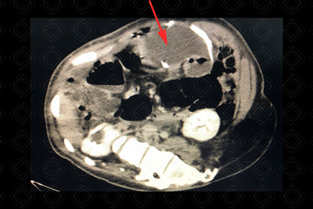

Descrição das figuras: P aciente de 9 anos, com disrafismo espinhal e mielomeningocele, com cateter de derivação ventriculoperitoneal, evoluindo com sinais de disfunção do shunt. Foi submetido à tomografia de abdome que evidenciou formação cística no mesogastro (setas vermelhas), envolvendo a extremidade distal do cateter de DVP, compatível com pseudocisto liquórico.

• Tomografia computadorizada do abdome: O bserva-se uma formação cística em geral, com grumos de debris e por vezes septos, envolvendo a extremidade do cateter. Essa lesão pode estar livre na cavidade peritoneal ou aderida a alguma intestinal, podendo causar um quadro de suboclusão intestinal (figuras acima).